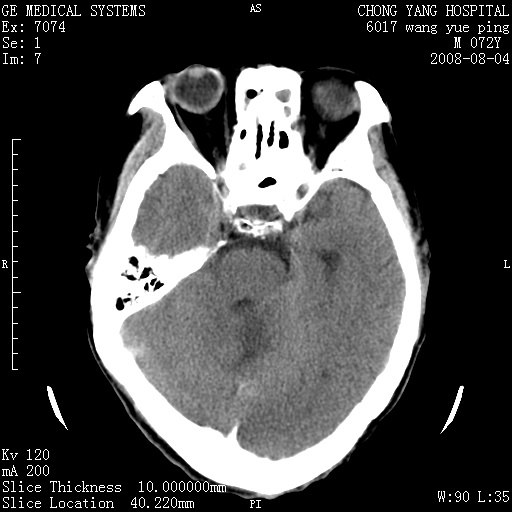

标题: CT14987:M72Y,头痛头昏,BP220/110. [打印本页]

标题: CT14987:M72Y,头痛头昏,BP220/110.

1)考虑左侧小脑脑梗塞。2)脑白质病。3)脑萎缩。4)双侧鼻腔新生物(息肉?)并阻塞性副鼻窦炎。

1.左侧小脑大面积梗塞;2.左侧基底节区腔梗;3.白质疏松;4.脑萎缩;5.慢性副鼻窦炎

小脑左侧病灶呈扇形分布,增强后未见明显瘤体样节结影,病变区未见强化。

支持:左侧小脑脑梗塞梗塞表现

另:脑白质病。脑萎缩。双侧鼻腔新生物(息肉?)并阻塞性副鼻窦炎。

1)考虑左侧小脑脑梗塞,建议治疗后复查除外其他,左基底节区腔隙性脑梗塞2)脑白质变性3)脑萎缩。4)双侧鼻腔新生物(息肉?)并阻塞性副鼻窦炎。